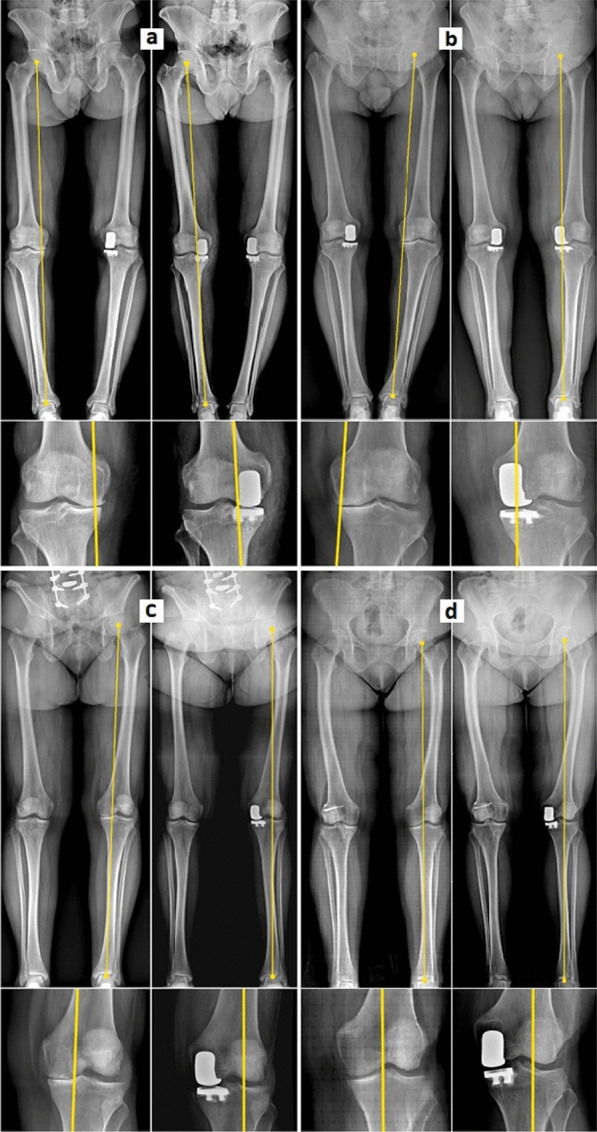

Coronal plane alignment of the knee (CPAK) classification and its impact on medial unicompartmental knee arthroplasty: exposing a unexpected external shift of limb mechanical axis in case of prearthritic constitutional valgus alignment: a retrospective radiographic study.